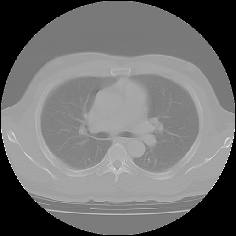

MPR表示について

CTやMRIなどの医療機器によって生成されたスライスシリーズ画像を表示する場合、MPR(多断面再構成)表示法は、非常に有効な読影方法であり、特に任意角度の斜断面画像の再構成(Oblique)表示法は、臨床診断に非常に有用かつ重要な読影手法となっています。

ImageClarityのMPR表示機能は、エンジンレベルで実現したもので、任意空間原点と任意3D方向の断面を表示することが可能になっており、補正表示をしながら実用レベルの高速表示を実現し、3D処理開発キットとしても非常に利用しやすいAPIを提供しています。 MPR以外に、任意サイズのMIP(最大値投影)表示法もサポートしています。

MPR/MIP表示